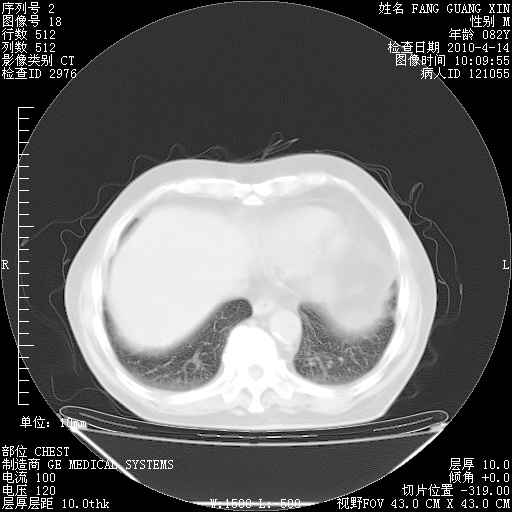

4月14日肺部CT

31.JPG

32.JPG

33.JPG

34.JPG

肺部CT平扫未见异常。